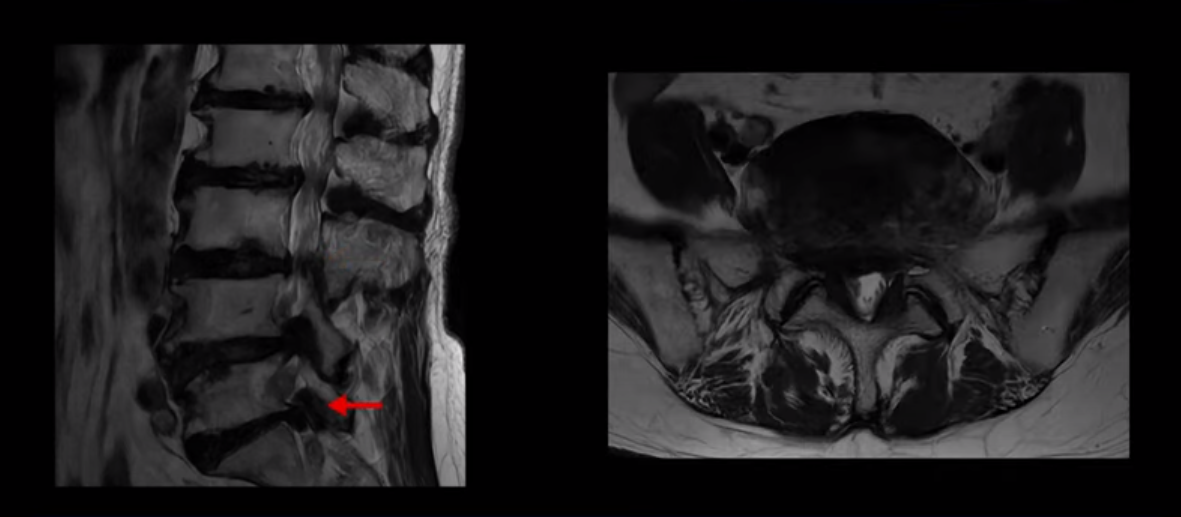

이 환자분은 MRI로 보면 허리 여러 마디가 신경이 매우 심하게 눌려 보이는 분입니다. 이분 MRI를 보면서 간단히 설명해 드린 후 어떻게 이렇게 신경이 심하게 눌린 환자분이 수술 없이 근육신경재활치료로 좋아질 수 있는지, 다리가 아파 걷지 못하는 환자가 어떻게 안 아프고 잘 걸을 수 있게 되는지, 10년 동안 괴로웠던 양 발의 시린 증상은 어떻게 사라질 수 있는지, 치료는 어떻게 하는지 자세히 설명 드리겠습니다.

MRI 보시면 (2-8) 허리의 5마디가 전부 다 심하게 퇴행되어 있습니다.

5마디 전부 다 심한 중심성 협착이 있습니다.

1번 2번,

2번 3번,

3번 4번,

4번 5번,

5번 6번

이렇게 모두 다 심하게 막히는 경우는 드문데요. 또한 오른쪽, 왼쪽 신경이 빠져나가는 추간공도 다 심하게 막혀있습니다.

오른쪽, 왼쪽 이렇게 신경 구멍들이 다 좁아지고 신경이 눌리니까 양쪽 다리가 발바닥까지 아파서 걷기 어렵고 양쪽 발이 10년 넘게 시린 겁니다. 당연히 수술해서 눌린 신경을 풀어줘야 한다고 들으셨는데요. 이런 환자분을 어떻게 수술 없이 치료할까요? 지금부터 설명해 드립니다.

이분 신경이 눌리는 증상은 오래됐지만, 증상이 아주 심해진 건 올해 들어와서입니다. 그럼, 이분 MRI 영상도 이렇게 심하게 안 좋아진 게 올해 들어와서일까요? 이분의 MRI로 보이는 협착은 아주 오래된 겁니다. 그래서 신경 구멍이 심하게 좁아진 것도 올해가 아니고 오래된 겁니다. 작년, 재작년에 훨씬 덜 아팠을 때 MRI를 찍었어도 신경 구멍 좁은 정도는 별반 차이가 없었을 겁니다.